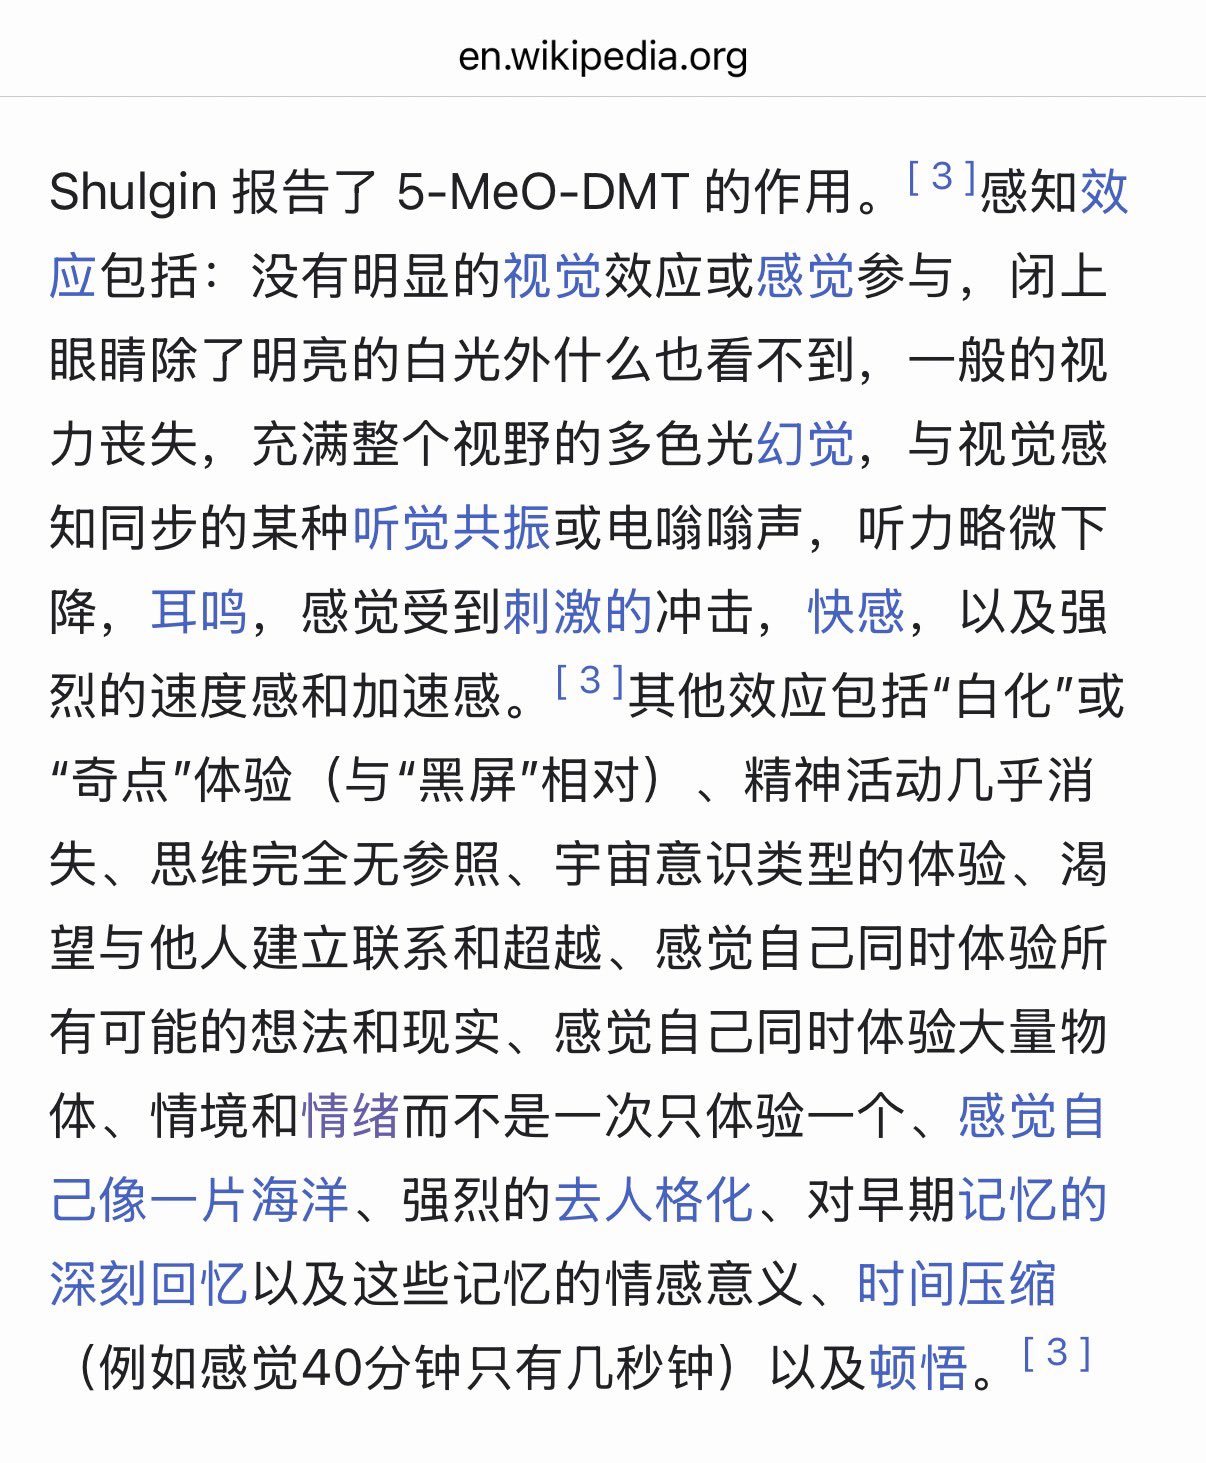

首先,从定义上讲,“反解离(anti-dissociative)”并不是一个标准的医学术语或者广泛认同的药理学分类。在正规资料,比如医学文献、维基百科、精神药理学教科书中,目前并没有“反解离药物”这个正式概念。

看上去像是为了描述某类特定效应而创造的术语(可能是nmda受体活性增强),用来对抗因NMDA受体拮抗剂(比如氯胺酮、DXM、PCP等)引发的解离体验(dissociation)。

那么更常见的是将其归入认知增强剂(cognitive enhancers),特别是改善认知连接性(connectivity)和现实感知(reality testing)的类型。

但其实在药理学上,单纯用“受体激动剂”来逆转“受体拮抗剂”的效应,有时会导致过度激活。

对于NMDA受体而言,过强的NMDA活化本身就与兴奋性毒性(excitotoxicity)和精神病样症状(psychotomimetic effects)有关,比如谷氨酸风暴可以引发严重的焦虑、妄想、乃至癫痫。

也就是说,简单地“激动-解除拮抗”在中枢神经系统是很危险的做法,尤其是对于易感个体(如有精神分裂素质的人)。

科学的处理方式一般是通过更细致的调节,比如微调NMDA/AMPA平衡、调节其他辅助途径(如GABA、5-HT、mGluR受体),而不是简单粗暴地用“NMDA增强剂”去顶回去。

而临床处理药物中毒中,其实医生更常用的做法是保守、支持性的治疗,比如补液,促进代谢,必要时镇静,以及监测生命体征防治并发症。

药物拮抗与受体激动之间,往往牵扯到的是复杂的适应性变化(receptor upregulation/downregulation),

不是简单的“给多一点刺激就能抵消”的关系